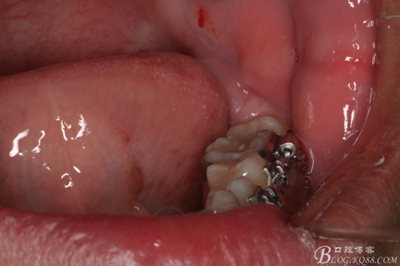

圖2.術(shù)前的口內(nèi)閉口位照片:上下牙列基本整齊